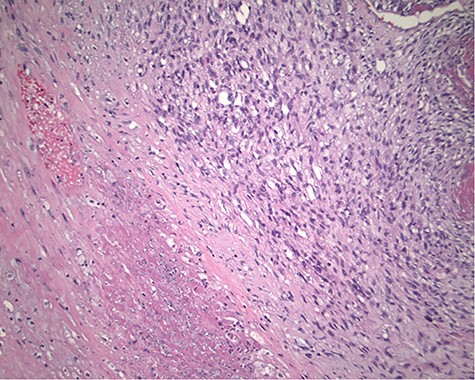

The pathology revealed a 282-g nodular tumor measuring 10.7 × 8.5 × 7 cm that was grossly tan, fibrotic and firm with focal yellow discoloration and soft flesh areas (Fig. 6). Microscopic analysis revealed high-grade spindle cell sarcoma arranged in intersecting fascicles with extensive areas of necrosis (Fig. 7). The lesional cells had fibrillary eosinophilic cytoplasm and evoid nuclei with nuclear pleomorphism (Fig. 8). Areas of rhabdomyoblastic and chondroid differentiation were also noted (Figs 9 and 10). Immunostaining was positive for desmin, focally for CD 34 and Bcl2, while Cam 5.2, CD117, S-100, SMA and HME45 immunostains show patchy staining for myogenin. Expression of H3K27me3 was completely lost in the tumor cells. MyoD1, SOX10, MDM2 and CDK4 were negative. It was identified as a high-grade MPNST with heterologous rhabdomyosarcomatous differentiation, i.e. MTT. All margins were negative.

Magnification 100×. Cellular spindle cell neoplasm with focal necrosis.

Magnification 200× Spindle cells with mild to moderate nuclear pleomorphism and focal rhabdomyoblastic differentiation.